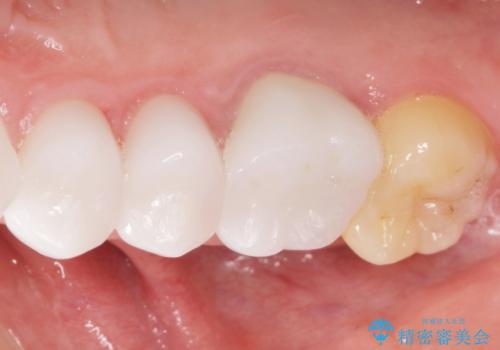

矯正治療とホワイトニングを提案しましたが希望されず、「接客関係の仕事で矯正治療は考えられない、短期間で治療を終わらせたい、ホワイトニングでは難しい位の人工的な白さにしたい」とのご要望により、治療前にワックスアップ模型を作製し何度もコンサルテーションを重ね、治療方針を決定しました。

歯頚ラインが変えられないことや天然歯を削るリスクをご理解頂いた上で、オールセラミッククラウンによる補綴治療を行いました。(見えない奥歯のみ天然歯のままとしました)

クラウンの色味に関して、自然な白さ(シェードA1~NW0.5)のクラウンを作製・試適したところ「もっと白くしたい」と希望され、当院で最も明度の高い色(シェードNW0)に修正しました。

被せ物の種類:オールセラミッククラウン スタンダード (シェード:NW0)